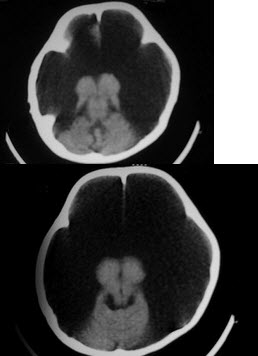

130、单项选择题

1岁,女,头颅呈球状,颅骨透光试验阳性,请结合CT图像选择最可能诊断()

A.脑严重缺血

B.慢性双侧性巨大硬膜下血肿

C.水瘤

D.先天性脑积水

E.外部性脑积水

131、单项选择题

1岁,女,头颅呈球状,颅骨透光试验阳性,请结合CT图片,选择最可能的诊断()

E.重度脑积水